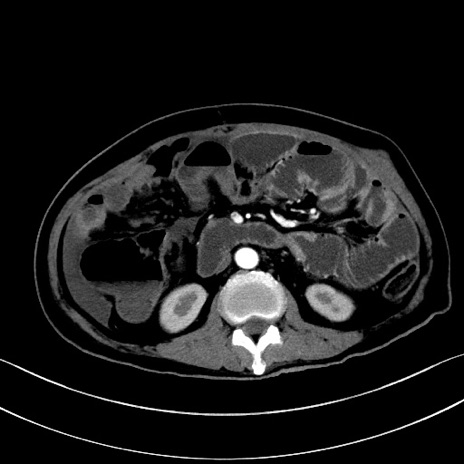

症例28(横断像)

【症例】60歳代男性

【主訴】嘔吐

【現病歴】胃癌にて胃全摘後。食思不振が悪化し、夜中に嘔吐することがある。

【既往歴】胃癌、胃全摘、脾摘、胆摘後

【データ】WBC 5900、CRP 10.56